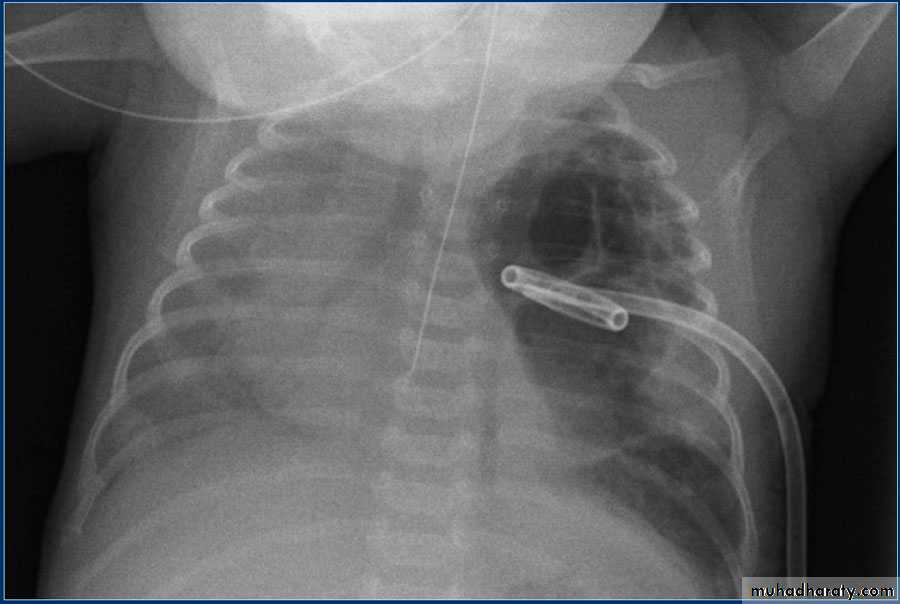

• Check up chest x-ray

• Malposition

Patient with fever, rigor and dyspnea